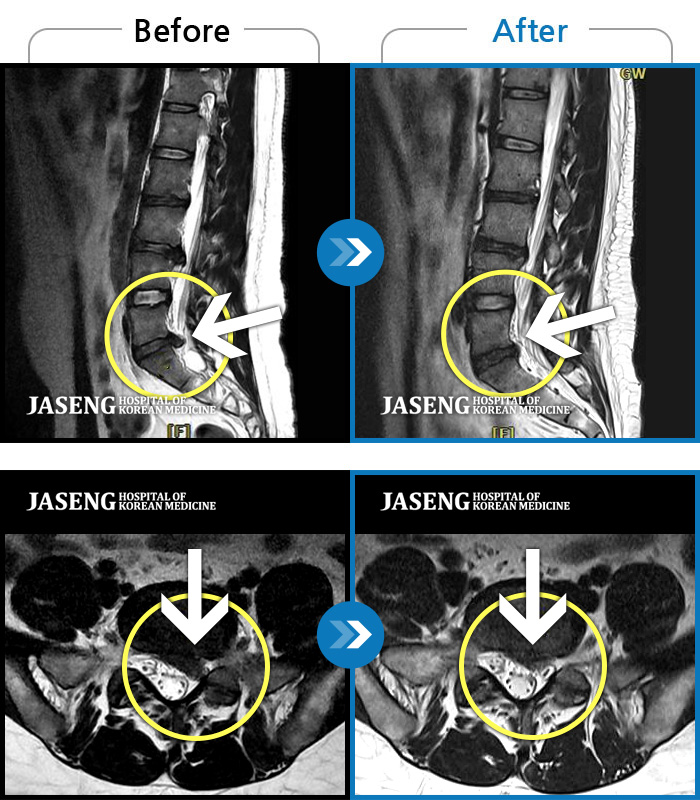

MRI로 보는 치료결과

1,169건의 MRI 전후 사진으로

터진 디스크 흡수 사례를 확인하세요.

[촬영시기:24.04.11~24.11.14]

[촬영시기:24.04.11~24.11.14]

[광주_허리디스크] 좌측 허리부터 골반 통증, 좌측 다리 감각 저하 증상으로 내원하셨습니다.조회수 2 2024.11.21 -